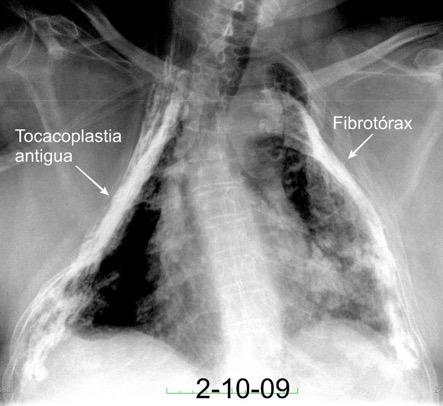

Paquipleuritis calcificada bilateral. En en lado derecho toracoplastia extensa con muñón residual pulmonar con bronquiectasias.

Fibrosis generalizada secundaria, casi siempre a post-empiema dando lugar a restricción y volumen pulmonar reducido.

Calcifica ocasionalmente. (Tb)

Redución de volumen

Fibrosis.

Basado en Kanne JP. Diffuse Pleural Thickening. Stern-Gurney. Expertdd.Chest. Mairsys. 2011 Fibrotórax .